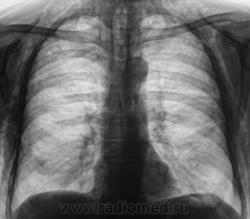

Шикарная эмфизема мягких тканей, перелом 8 -го ребра справа по задней подмышечной линии (как минимум)....

Этого пациента, сегодня дали на контроль. Первичная рентгенограмма от 8.05., там плюсом, имело место коллабирование правого легкого на 2/3.

Да весьма показательный, яркий случай!

А справа в нижних отделах кальцинат?